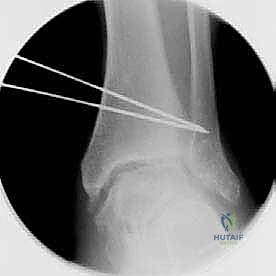

- قص العظم (Osteotomy): باستخدام منشار جراحي دقيق وموجهات خاصة، يتم قص عظم الظنبوب (وفي بعض الأحيان عظم الشظية أيضاً) بالزاوية التي تم تحديدها مسبقاً في التخطيط الثلاثي الأبعاد.

- تصحيح المحور: يتم فتح أو إغلاق الشق العظمي للوصول إلى المحور الميكانيكي السليم للكاحل. يتم التحقق من ذلك داخل غرفة العمليات باستخدام جهاز الأشعة السينية الفلوروسكوبي (C-arm).